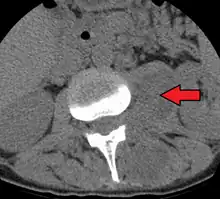

Psoas abscess is a collection of pus (abscess) in the iliopsoas muscle compartment.[1][2] It can be classified into primary psoas abscess (caused by hematogenous or lymphatic spread of a pathogen) and secondary psoas abscess (resulting from contiguous spread from an adjacent infectious focus).[2]

Psoas abscess may be caused by lumbar tuberculosis, vertebral osteomyelitis, and pyelonephritis. Patients with Crohn's disease, diabetes, or immunocompromised states are at a higher risk of developing a psoas abscess.

Symptoms include flank pain, fever, and an inguinal mass. A positive psoas sign should raise suspicion of psoas abscess as a possibility. Owing to the proximal attachments of the iliopsoas, such an abscess may drain inferiorly into the upper medial thigh and present as a swelling in the region. The sheath of the muscle arises from the lumbar vertebrae and the intervertebral discs between the vertebrae. The disc is more susceptible to infection, from tuberculosis and Salmonella discitis. The infection can spread into the psoas muscle sheath.[3]